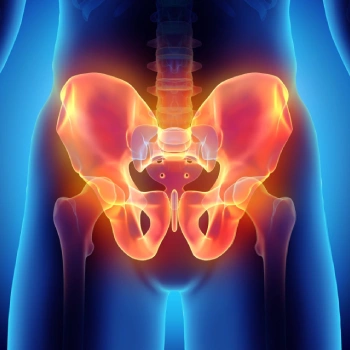

در این روش تصویر برداری یک صفحه (گیرنده یا دتکتور) در زیر عضو و قسمت مورد نظر قرار داده می شود و اشعه ایکس(دُز از اشعه جهت تشخیص) به همان قسمت که روی صفحه قرار گرفته تابنده می شود و توسط صفحه اطلاعات دریافت می شوند و همین اطلاعات پس از پردازش های لازم در نهایت عکس رادیولوژی به ما ارائه می دهد. کاربردهای رادیولوژی در منزل دقیقاً همان کاربرد رادیولوژی در بیمارستان ها می باشد از جمله بررسی انواع شکستگی ها، دررفتگی مفاصل، آرتروز مفاصل، دیدن پروتز های داخل استخوان از نظر بررسی موقعیت پروتز، آب آوردگی ریه(اِدم وافیوژن) و عفونت ریه، شکستگی دنده ها، انساد و وجود هوا در شکم و… می باشند. رادیولوژی در منزل تمام این خدمات را ارائه می دهد.

تصاویری از رادیولوژی در منزل توسط گاما پرتو